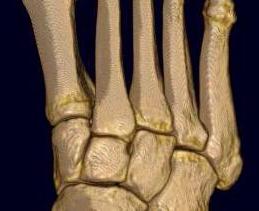

Classification

| Isolated | Homolateral | Divergent |

|---|---|---|

| Only 1st MT injured / displaced | All 5 metatarsals displaced in same direction |

1st metatarsal displaces medially Other 4 metatarsals displace laterally |

| Most common | Least common | |